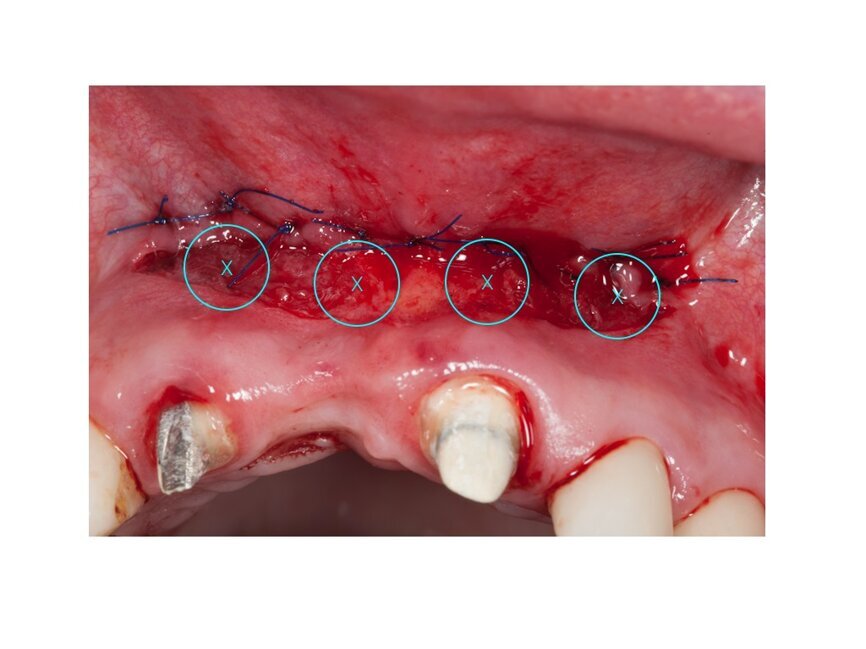

Na podstawie uzyskanych danych zasugerowano pacjentce etapowe rozwiązanie zaistniałej sytuacji, na co uzyskano zgodę. Pierwszy etap obejmował frenulotomię i westibiloplastykę w celu uzyskania poprawy zastanych warunków pod względem tkanek miękkich. Zaplanowano dowierzchołkowe przesunięcie płata śluzówkowego z pozostawieniem okostnej. Zabieg przecięcia błony śluzowej przeprowadzono przy użyciu lasera Er:YAG przy następujących ustawieniach: VLP 120 mJ, 20 Hz, a następnie przesunięty dowierzchołkowo płat błony śluzowej wraz z przyczepami mięśni przyszyto szwami materacowymi Prolene 5.0 do okostnej (Ryc. 4). Następnie, przy użyciu głowicy Genova i lasera Nd:YAG o parametrach: MSP, 0,5 W, 20 Hz dokonano naświetlenia rany w 4 miejscach po 60 s na punkt (Ryc. 5-7).

Ryc. 7_Zabieg biomodulacji w 4 punktach.